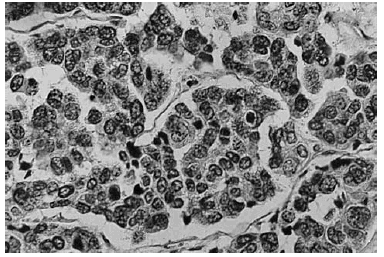

La zona correspondiente al nódulo ulcerado se correspondía con una lesión tumoral de color basófilo, que en su superficie presentaba continuidad con la epidermis y estaba en parte ulcerada. La tumoración ocupa la dermis, llegando en profundidad hasta el tejido celular subcutáneo (fig. 3) y estaba compuesta por nidos y cordones de células epiteliales muy anaplásicas, con núcleos vesiculosos y citoplasma escaso, con frecuentes monstruosidades celulares y alto índice de mitosis, siendo muchas de ellas atípicas (fig. 4). El diagnóstico fue de carcinoma espinocelular basaloide invasivo (Bowen invasivo).

Fig. 3.--Aspecto de la lesión nodular invasiva formada por nódulos basaloides.

vFig. 4.--Detalle de los nódulos basaloides.